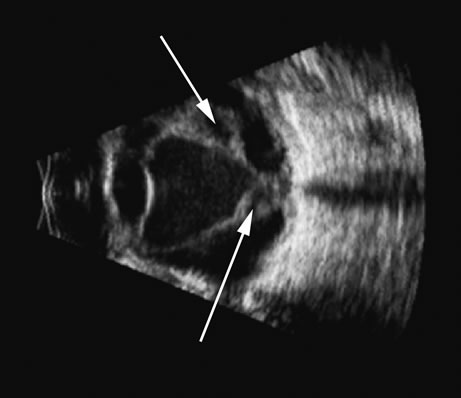

Fresh blood in the vitreous may be acoustically clear since the red cells may not have congealed sufficiently to form a good echo-producing surface.8 A retracted “hyaloid” or posterior limiting membrane (PLM) of the vitreous can be shown with most B-scan instruments, but paradoxically a retracted vitreous may not be seen as well with higher-resolution, more highly focused transducers because they display less area of the reflective surface. Blood collected on the surface of the PLM enhances this surface and may, in some cases, make the PLM resemble a detached retina, since its anatomic dimensions can be similar to the retina. Three differences may help distinguish the two structures. First, kinetic scanning reveals a lack of attachment at the optic nerve for a PLM. Second, the PLM is irregular in reflection and thickness (usually thicker than the retina) between the ora and the disc, and usually the surface cannot be traced forward to the ora on the B-scan display. Third, the amplitude of the echoes from the PLM is lower than from the retina, except when directly perpendicular to the beam, where they may be similar in amplitude. Many of these features of a PLM are demonstrated in Figure 7, whereas Figure 8 shows a typical detached retina.

Fig. 7. This B-scan ultrasonogram demonstrates retinitis proliferans with typical vitreous membrane attaching to the proliferative membrane (arrows) that can resemble a traction detachment. Scanning at right angles helps distinguish proliferative membranes from retinal traction membranes, as they have less reflectivity than retina.

Fig. 8. A retinal detachment (arrow) is very easily detected as a high-amplitude, usually relatively rigid or gently wafting structure connecting always to the optic nerve head in a complete detachment, and usually traceable anterior to the ora serrata. Variations of this pattern can be seen, depending on the plane of the cut and the extent of the detachment, but the height of the echo on A-scan should always be maximal in order to differentiate retina from other, similar membrane formations.